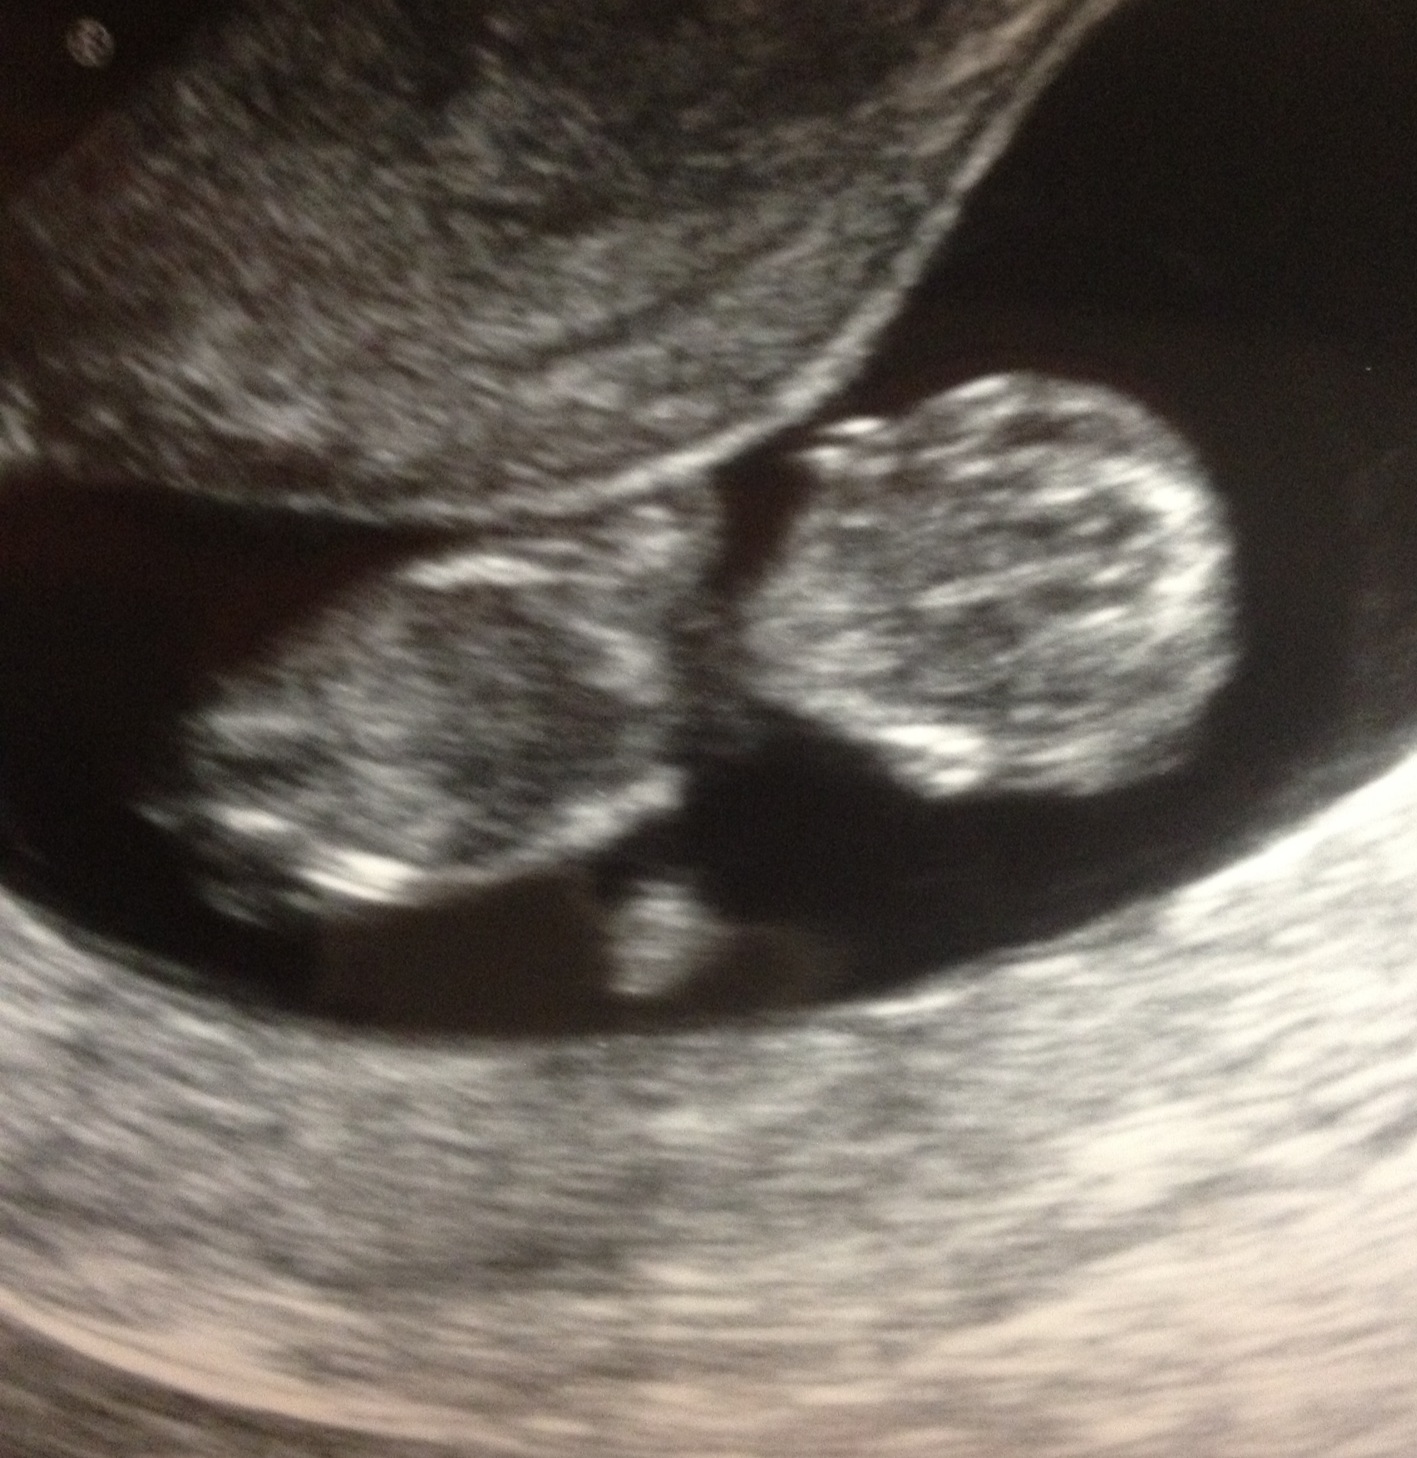

Yay Sticky Rainbow! You’re still growing!! You look so much more human-like now! We had another ultrasound on Friday 12/30/11. So your actual age was 10 weeks 4 days. Your heartbeat was 174 bpm and looking great! I have continuing problems with spotting, so the Drs are watching me very closely to make sure you’re okay. But you’re a trooper!! You’re continuing to make Mommy suuuuuper sick. I told Daddy it was his satan spawn doing it to me, and he said it was my deviled egg

Here is your ultrasound pic from Friday: look at your cute little ears and hand!